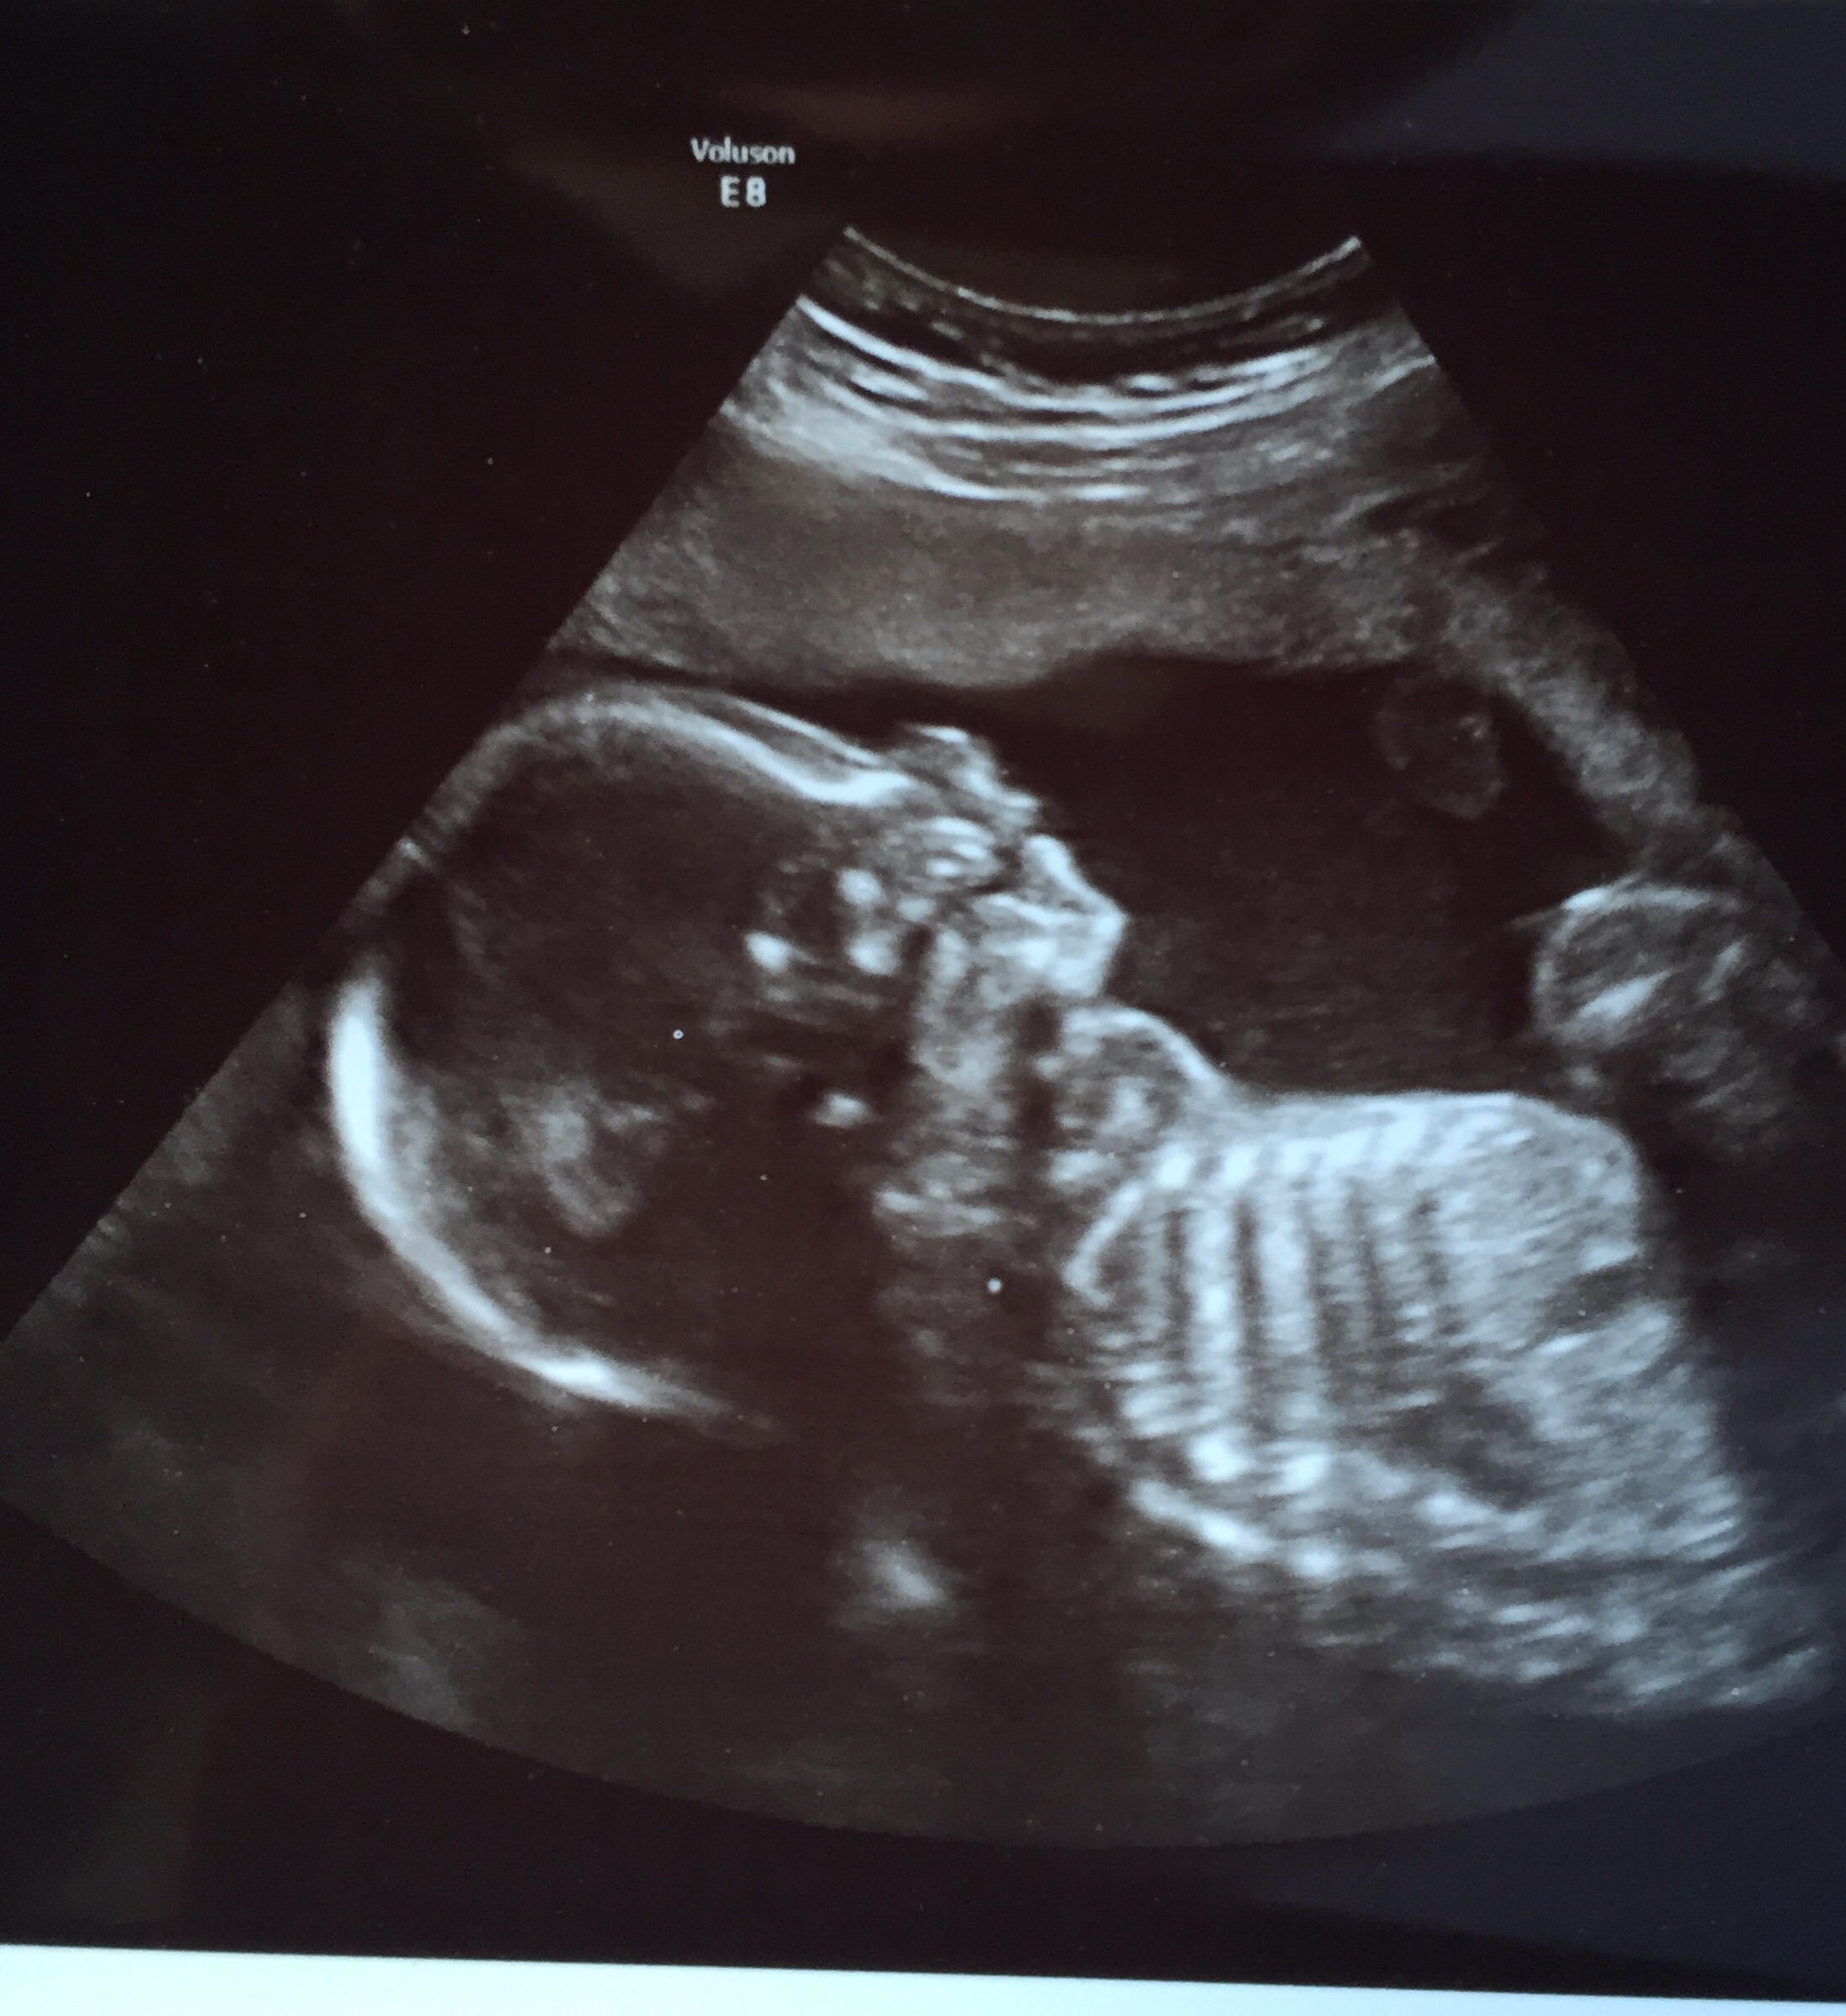

23 weeks! Please excuse my sloppiness, Im battling a nasty cold. That was the best I could do! U/S is from our Echocardiogram on Monday. Baby girl's heart looks perfect!